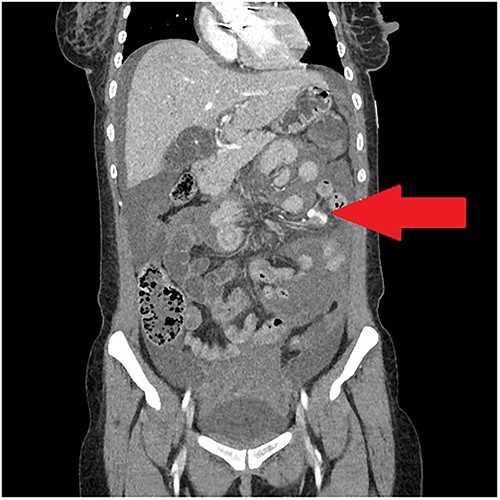

A 30-year-old woman was admitted with erratic behaviour and fever and found to have Staphylococcus aureus bacteraemia. She had a history of intravenous drug use and previous mechanical aortic valve replacement (AVR). Echocardiogram as part of her initial workup demonstrated aortic root abscess with evidence of septic emboli in the brain, spleen and bilateral kidneys. She underwent revision of AVR and warfarin was re-commenced. She remained an inpatient for ongoing intravenous antibiotics. After 2 weeks, she complained of severe abdominal pain, shortness of breath and dizziness. Over a period of hours, she became progressively tachycardic and hypotensive. A haemoglobin taken several hours after onset of pain was 76 g/L, representing a 25 g/L decrease from her baseline. WCC was elevated at 15 and INR was subtherapeutic at 2.2. Abdominal computed tomography (CT) with IV contrast demonstrated contrast material extravasating within the small bowel mesentery consistent with active bleeding (Fig. 1).

Portal-venous phase CT abdomen demonstrating haemoperitoneum and contrast extravasation in small bowel mesentery.